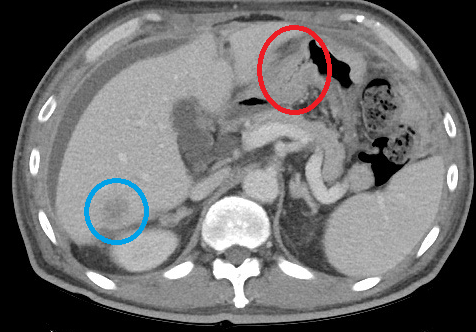

Img | CT: Distal stomach obstruction, liver hypoattenuated nodule (r/o metastasis) |

• 아직 병리적 확진이 없지만 staging을 위해 시행한 CT에서 distal stomach의 심한 obstruction과 간에 metastasis로 추정되는 nodule이 하나 확인되고, ascites도 보인다. Metastasis 소견이 있으므로 distal gastrectomy, tTotal gastrectomy와 같은 근치적 목적의 수술적 치료를 시행할 수 없다고 판단된다. 따라서, 근치적 목적의 치료보다는 obstruction을 palliative하게 해결할 수 있는 위스텐트삽입이 적절하다.

• 빨간색 원 부분에서 distal stomach obstruction을 확인할 수 있으며, 파란색 원을 통해 간으로의 전이를 의심해 볼 수 있다.